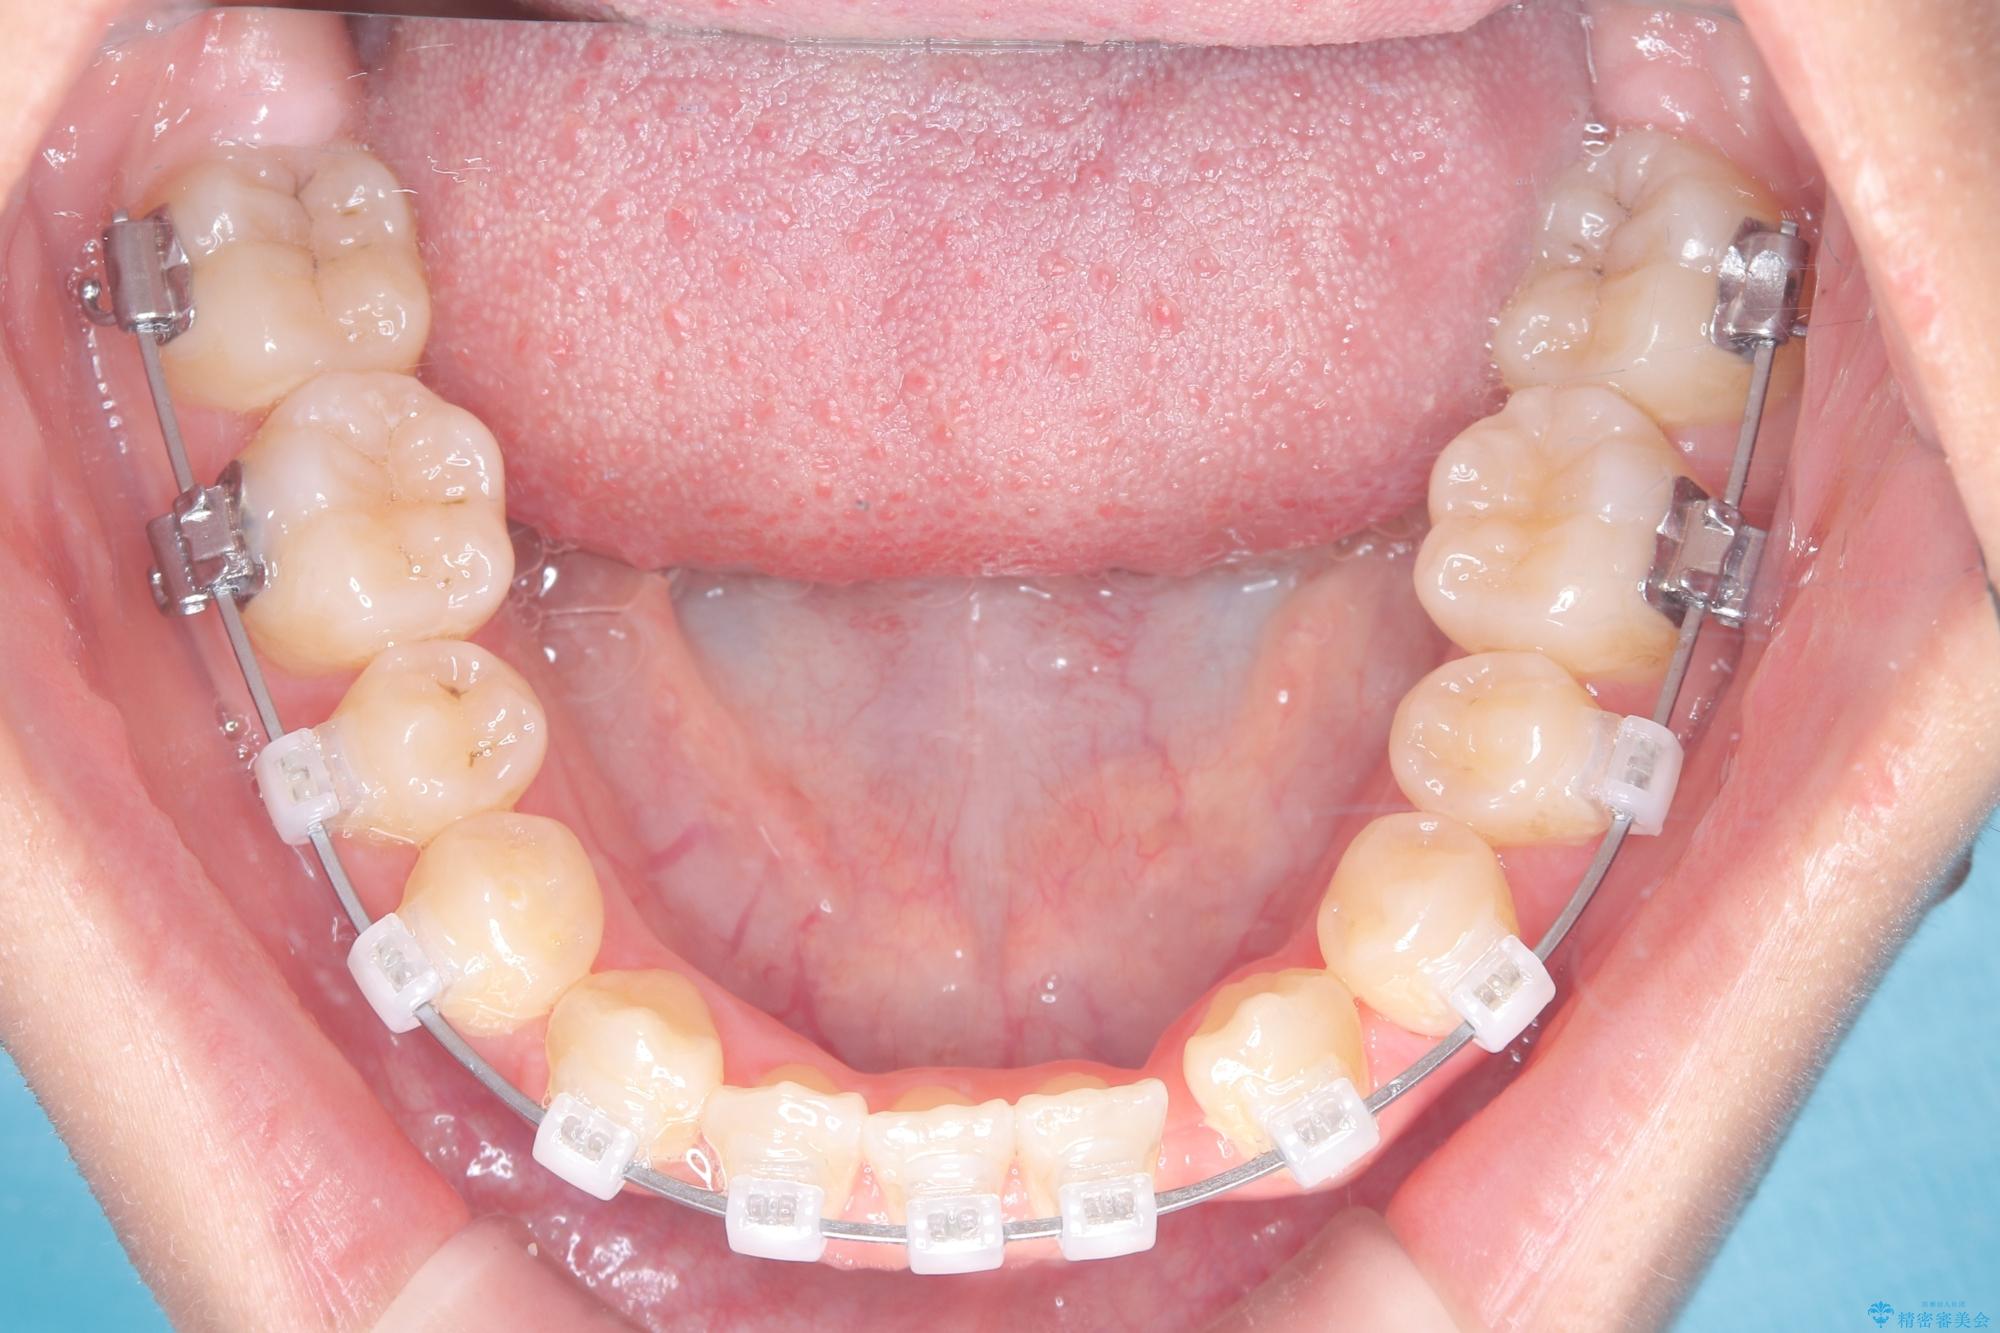

診査の結果、すでに下顎前歯の抜歯が行われていましたが、マウスピースの適合が著しく悪くなっており、歯が計画通りに動いていない状態でした。また、歯を支える骨の厚みや歯肉の薄さを考慮すると、このままマウスピースによる傾斜移動を続けるのは歯肉退縮(歯茎が下がること)のリスクが非常に高いと判断。

安全かつ確実に抜歯スペースを閉じ、咬み合わせを完成させるため、マウスピースから**ワイヤー矯正(マルチブラケット装置)**へ切り替えるリカバリープランを提案しました。

装置の変更と歯肉への配慮: ワイヤー矯正は歯の根(歯根)を平行に移動させる「歯体移動」を得意としています。本症例では、歯肉退縮を防ぐために、歯の傾きを精密にコントロールしながら抜歯スペースを閉じる必要がありました。ワイヤー装置を用いることで、インビザラインでは難しくなっていた三次元的な細かい調整を可能にしました。